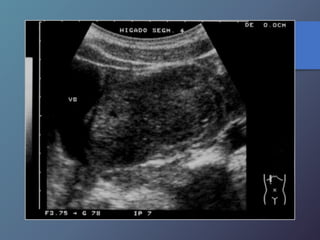

Mt Hiperecoicas

• Ecográficamente se presentan las lesiones

de tamaño variable con presencia de un

halo hipoecoico.

• Diferenciar lesiones malignas de benignas

por presencia de halo hipoecoico.

• Se describen como lesiones ecógenas,

hipoecoicas, en diana, calcificadas,

quísticas y difusas.

Clasificación de las Metástasis

MT ecogenas:

• origen digestivo o chc.

MT hipoecoicas:

• Son hipovasculares.

• Origen CA de mamas, pulmón, páncreas y esófago.

• Los linfomas hepáticos pueden manifestarse en masas

hipoecoicas, o difusas difíciles de diferenciar por ecografía

o TC.